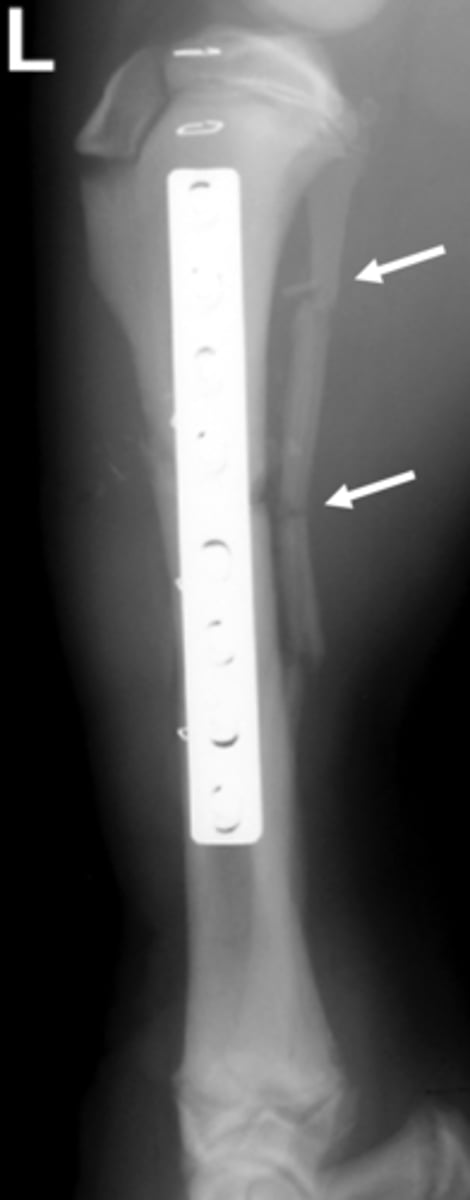

What is this an example of?

Malunion

What is a malunion?

the healing of a bone in a nonanatomic position